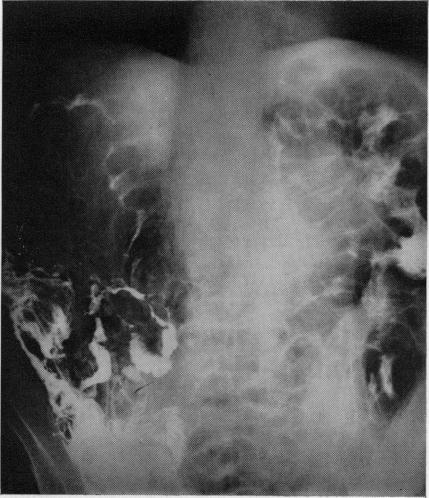

肠壁囊样积气症

Pneumatosis cystoides intestinalis.

A brief outline of the aetiology and pathogenesis of pneumatosis cystoides intestinalis is given followed by a review of four cases which have occurred in the Glasgow area recently. The radiological appearances of the condition are considered in detail.

摘要